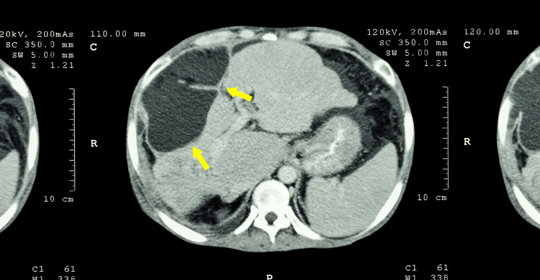

微波消融是在超音波或CT引導下將微波天線插入腫瘤體內,啟動微波能量產生高溫,使腫瘤組織凝固壞死。微波消融適用於直徑小於3公分的肝癌,它可以直接作用於腫瘤組織,引起蛋白質變性並破壞細胞結構,從而達到消滅腫瘤的目的。